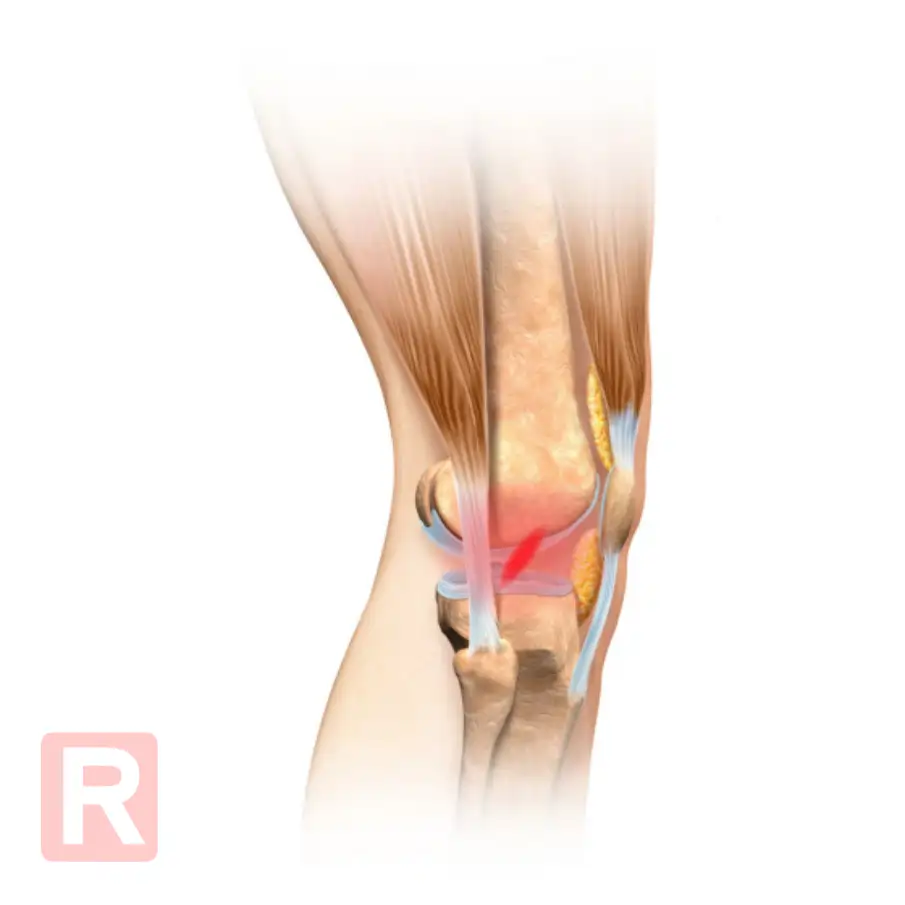

Rekonstrukcja więzadła krzyżowego przedniego (ACL) to jeden z najczęściej wykonywanych zabiegów ortopedycznych wśród osób aktywnych fizycznie, a także sportowców. Jednak sam zabieg to dopiero początek – kluczowy dla sukcesu jest proces rehabilitacji, który musi być odpowiednio zaplanowany i realizowany konsekwentnie.

Rehabilitacja po rekonstrukcji ACL zaczyna się niemal natychmiast po operacji – najczęściej w pierwszej lub drugiej dobie. Działanie w odpowiednim momencie ma kluczowe znaczenie, ponieważ zmniejsza ryzyko powikłań, takich jak zrosty, sztywność stawu czy osłabienie mięśni.

Szyna CPM (Continuous Passive Motion) odgrywa istotną rolę w pierwszych tygodniach po operacji ACL. Ponieważ porusza kolanem za pacjenta, zapewnia: